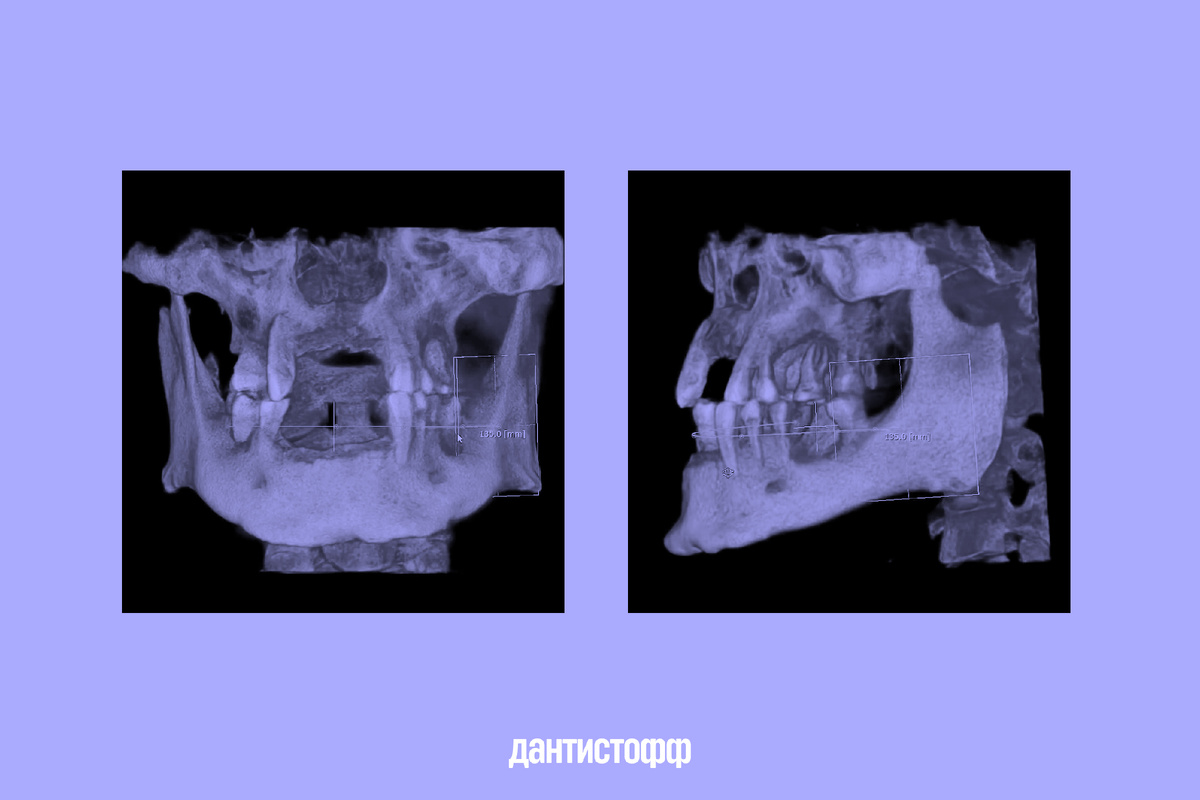

Снимки моей челюсти

Сначала врачи провели диагностику. Она помогла выяснить, что у меня глубокая атрофия костной ткани и дёсен, поэтому нужно обязательно наращивать костную ткань — иначе имплантаты не приживаются.